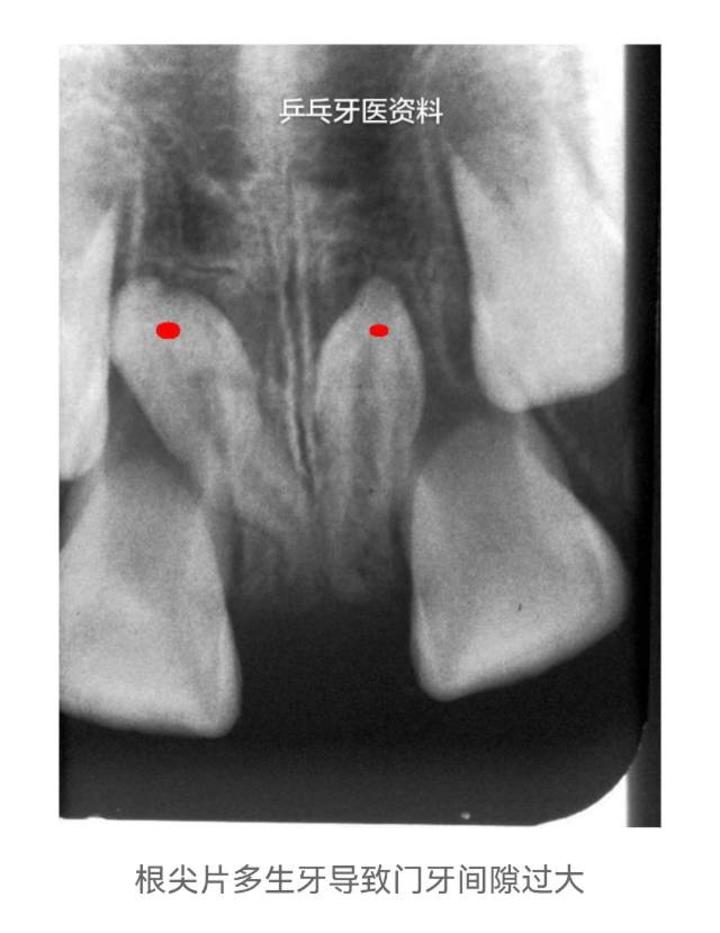

1.门牙间隙